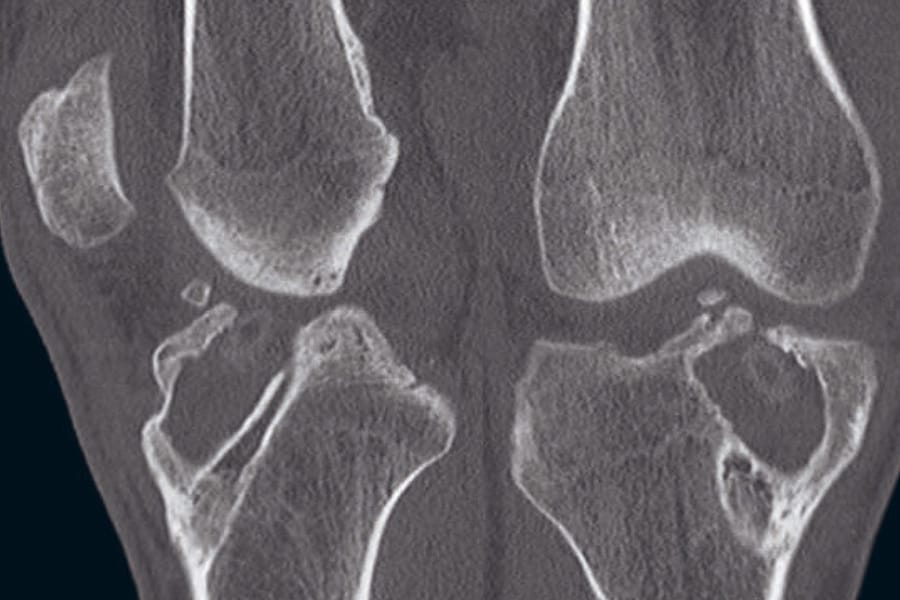

The articles in this issue address intersecting dimensions of ACL surgery. Management of combined injuries of the ACL and medial knee and the interaction between anterior cruciate ligament and tibial slope, including the role of tibial deflexion osteotomy, examine current approaches to complex knee pathology. Practical strategies for dealing with bone tunnels in revision ACL reconstruction offer technical guidance for reoperative cases. The issue further extends to perioperative care, exploring immersive virtual reality as a means to potentiate hypnosis in surgical support.